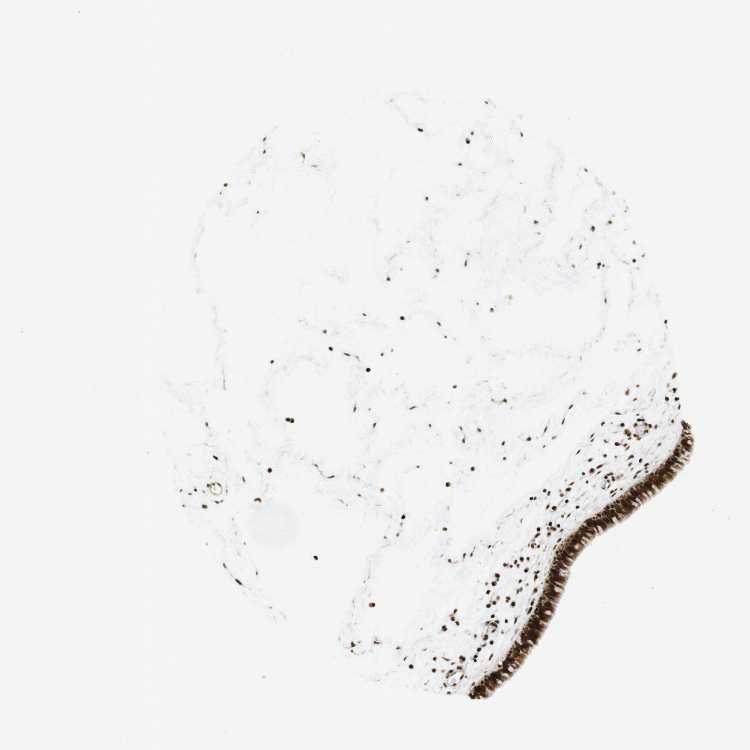

TISSUE PRIMARY DATA NASOPHARYNX Show tissue menu

NASOPHARYNX - Antibody stainingi

Antibody staining in the annotated cell types in the current human tissue is reported as not detected, low, medium, or high, based on conventional immunohistochemistry profiling in selected tissues. This score is based on the combination of the staining intensity and fraction of stained cells.

Each image is clickable and will lead to virtual microscopy that enables deeper exploration of all samples and also displays staining intensity scores, fraction scores and subcellular localization as well as patient and tissue information for each sample.

Antibody HPA067966Antibody CAB012432

Basal cells Not detected-

Ciliated cells (cell body) Medium-

Ciliated cells (cilia axoneme) Not detected-

Ciliated cells (ciliary rootlets) Medium-

Ciliated cells (tip of cilia) Not detected-

Goblet cells Not detected-

Respiratory epithelial cells -High